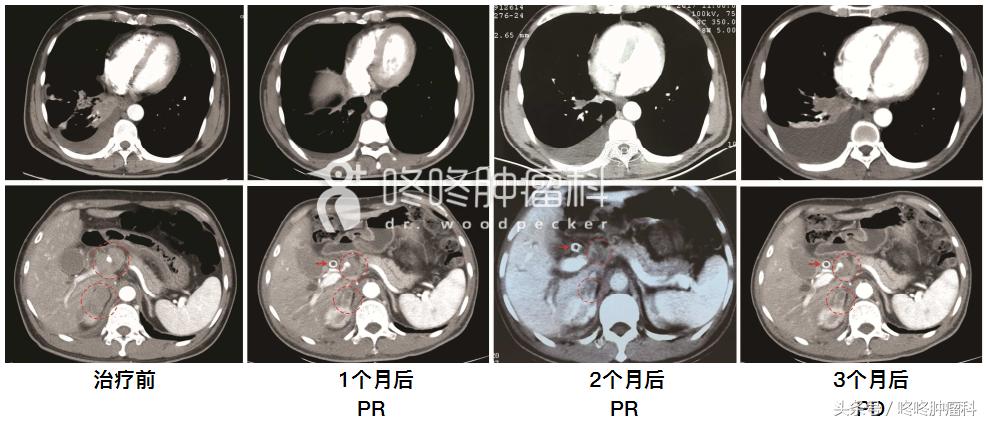

吴一龙教授报道了一例43岁男性晚期肺腺癌患者,一开始是EGFR 19缺失突变,接受阿法替尼治疗,部分缓解,疗效维持了12.8个月;再次穿刺活检发现,出现了T790M突变,于是开始吃AZD9291,部分缓解,疗效维持了7.4个月。然后再次出现腹腔淋巴结增大、一般情况恶化。抽血做基因检测,发现该患者又出现了C797S突变,同时为反式突变。于是,又给他安排了AZD9291联合特罗凯的治疗,服药两个月后,肿瘤部分缓解,血液基因检测发现T790M突变和C797S突变消失,但是原有的19外显子缺失突变依然存在。继续服药,3个月的时候,患者胸水增多,疾病进展。再次基因检测,发现患者19外显子缺失突变、T790M突变以及C797S突变都有;而且令人震惊的是,这一回C797S突变变成了顺式突变;随后,患者又换了一个国产的第三代靶向药,无效;最终换成了化疗,一般情况才改善。下图是这位患者在接受AZD9291联合特罗凯治疗前后的CT变化: